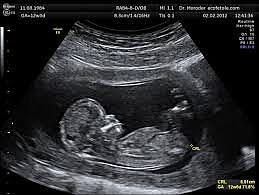

-The 2D

On June 7, 1958.